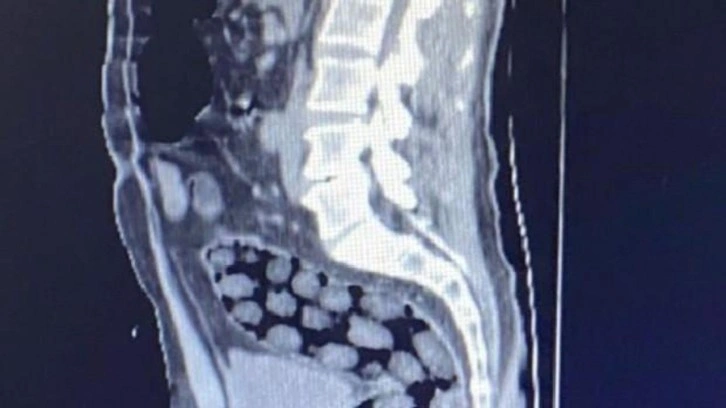

Bitlis Valiliğinden yapılan açıklamada,  uyuşturucu ile mücadele kapsamında elde edilen istihbari bilgiler doğrultusunda Tatvan’da durdurulan bir otobüste yabancı uyruklu 3 yolcunun yakalandığı belirtildi. Açıklamada, “Bitlis Emniyet Müdürlüğü Narkotik Suçlarla Mücadele Şube Müdürlüğü ve İstihbarat Şube Müdürlüğü ekiplerince gözaltına alınan ve Tatvan Devlet Hastanesine sevk edilen şüphelilerin röntgen ve tomografi görüntülerinde mide ile bağırsaklarında çok sayıda yabancı cisim bulunduğu tespit edilmiş, yapılan tıbbi müdahale ile şüphelilerin  paketleyerek yuttuğu toplam 91 adet daralı ağırlığı 1 kilo 126 gram metamfetamin maddesine el konulmuştur. Şüpheliler, çıkarıldığı adli mercilerce tutuklanarak cezaevine gönderilmiştir. Hemşehrilerimizin huzuru ve güvenliği için uyuşturucu madde imalatı, kaçakçılığı ve kullanımına karşı yürütülen kararlı mücadelemiz devam edecektir” denildi.

Açıklamada, “Bitlis Emniyet Müdürlüğü Narkotik Suçlarla Mücadele Şube Müdürlüğü ve İstihbarat Şube Müdürlüğü ekiplerince gözaltına alınan ve Tatvan Devlet Hastanesine sevk edilen şüphelilerin röntgen ve tomografi görüntülerinde mide ile bağırsaklarında çok sayıda yabancı cisim bulunduğu tespit edilmiş, yapılan tıbbi müdahale ile şüphelilerin  paketleyerek yuttuğu toplam 91 adet daralı ağırlığı 1 kilo 126 gram metamfetamin maddesine el konulmuştur. Şüpheliler, çıkarıldığı adli mercilerce tutuklanarak cezaevine gönderilmiştir. Hemşehrilerimizin huzuru ve güvenliği için uyuşturucu madde imalatı, kaçakçılığı ve kullanımına karşı yürütülen kararlı mücadelemiz devam edecektir” denildi.